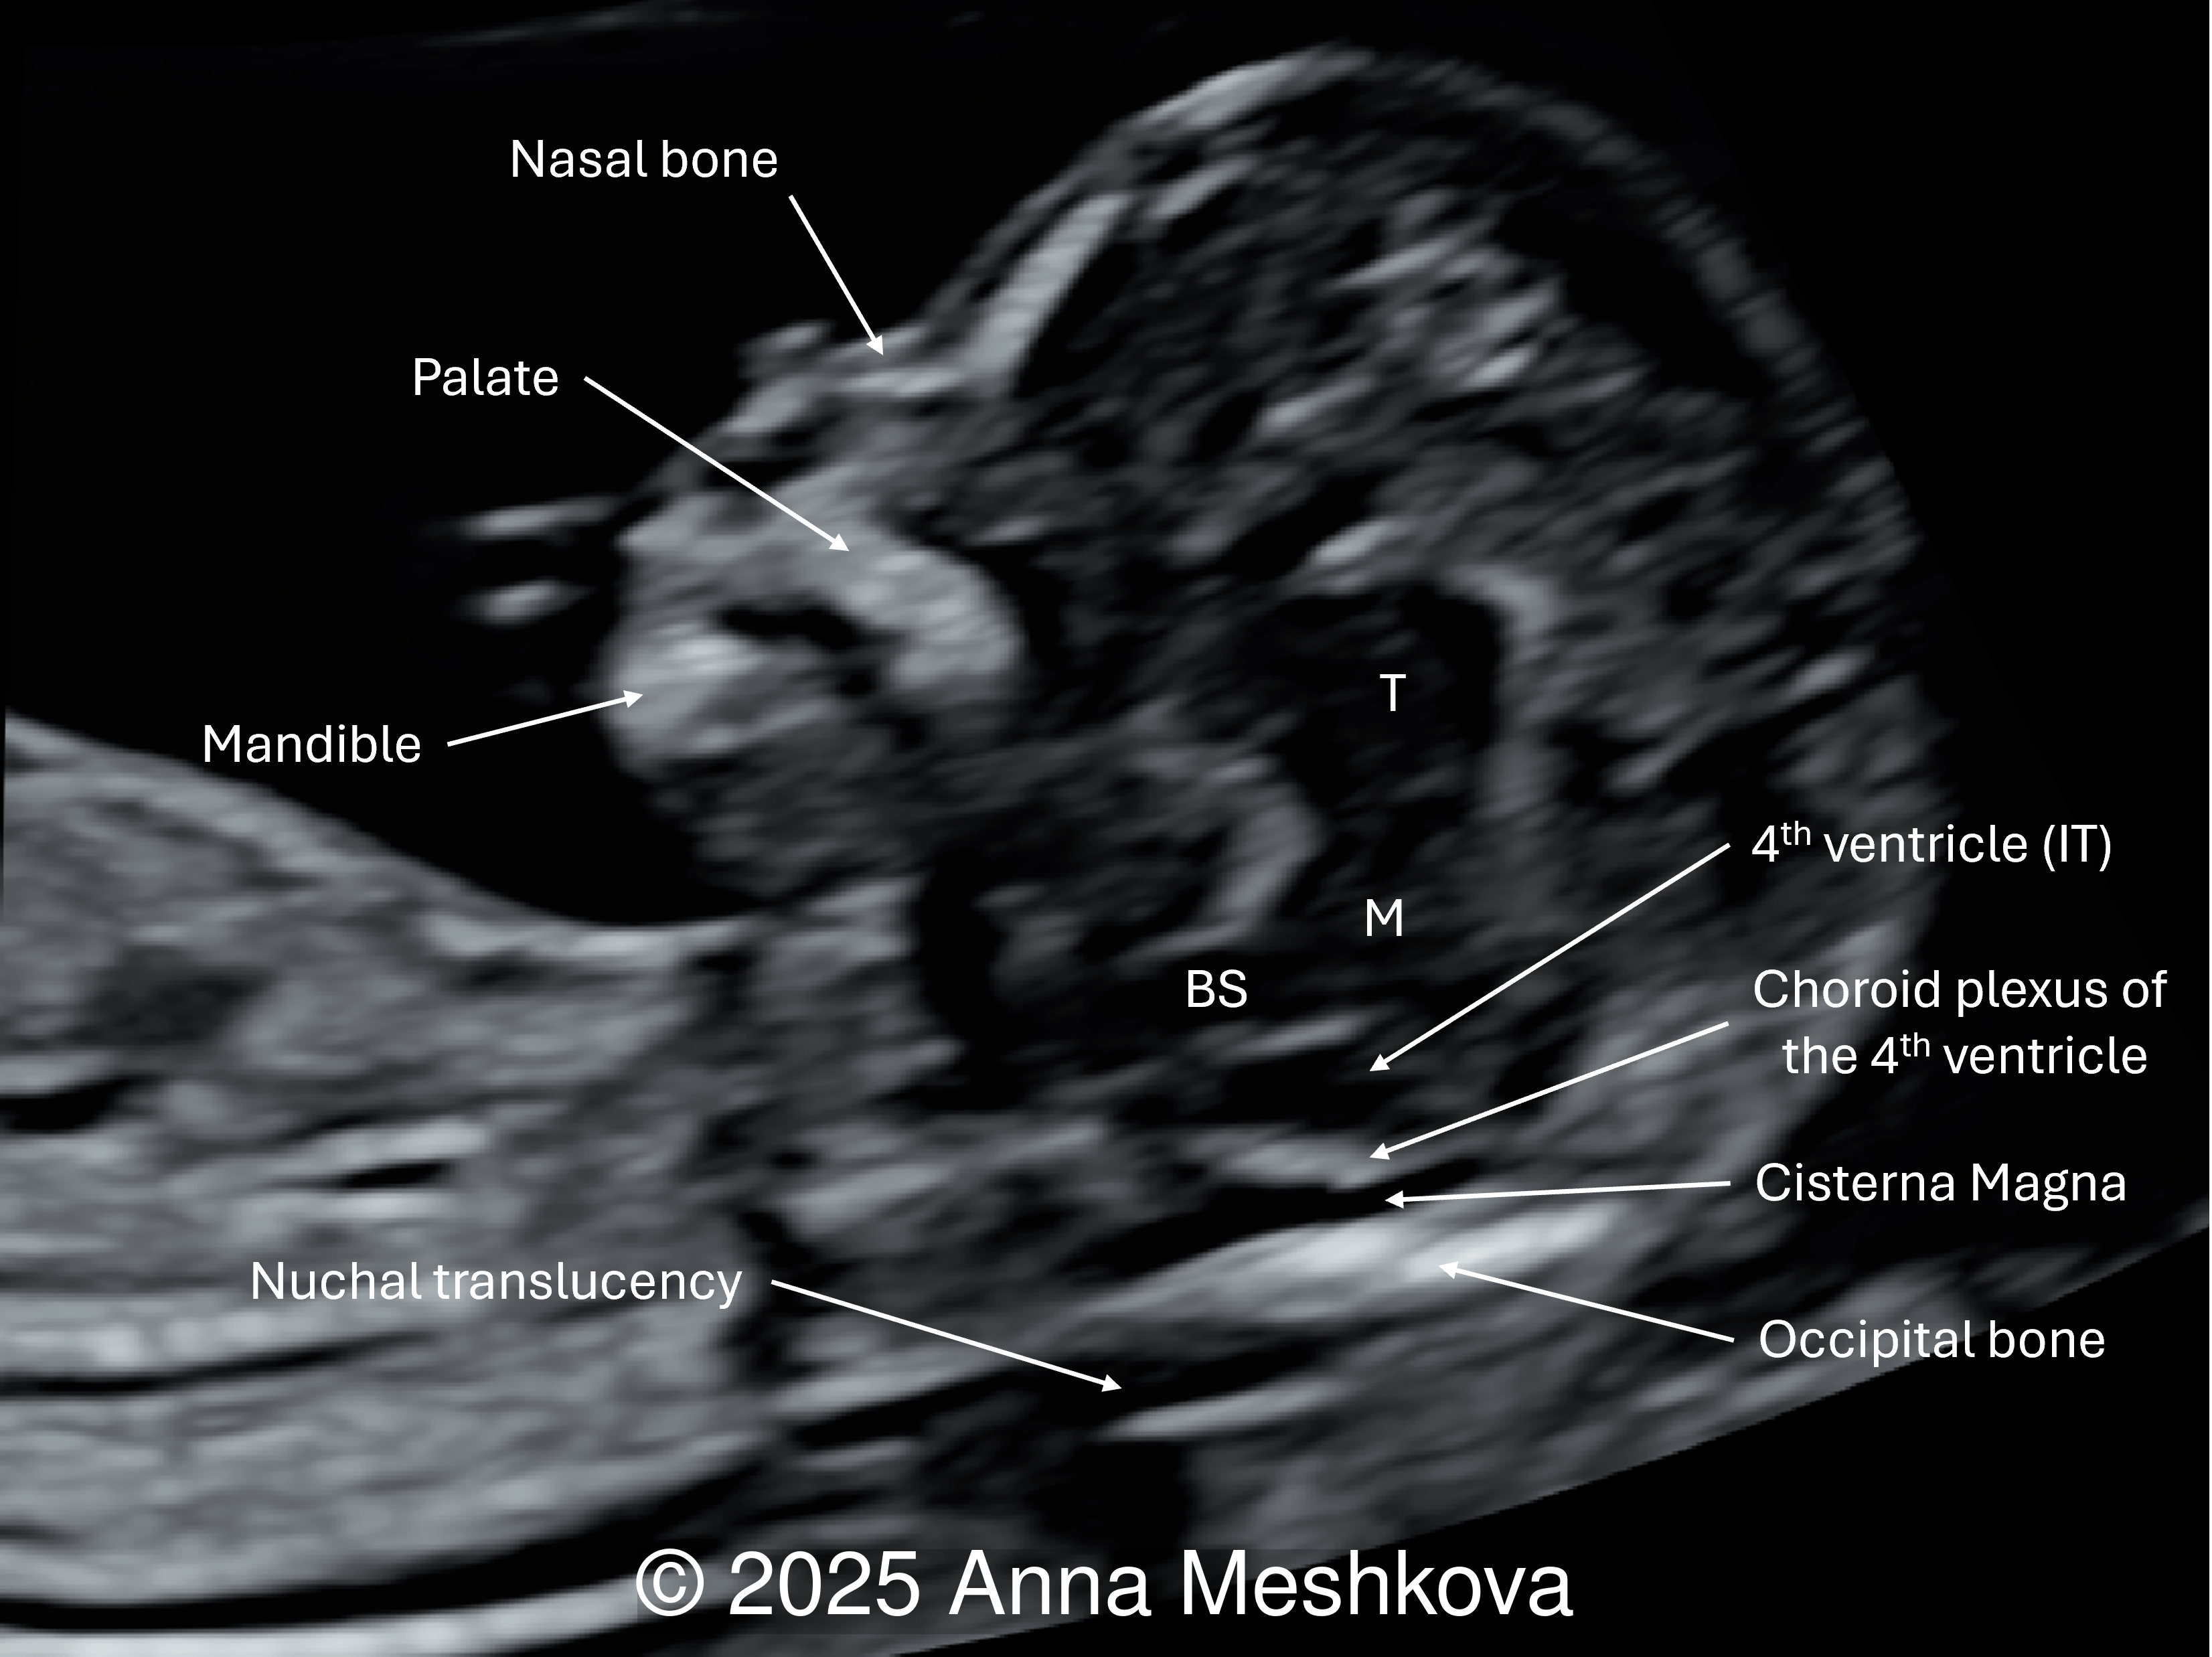

1. Intracranial translucency (IT) represents the fourth ventricle, which appears as a hypoechoic space in the mid-sagittal view of the fetal face. In open spina bifida, intracranial translucency may be absent or compressed due to Arnold-Chiari II malformation [1].

Normal fetus with intracranial translucency (IT) appearing as a fluid-filled space between the brainstem (BS) anteriorly and the choroid plexus of the 4th ventricle posteriorly. The future cisterna magna is present. (T: thalamus; M: midbrain)

Image 3 Normal fetus with intracranial translucency (IT) appearing as a fluid-filled space between the brainstem (BS) anteriorly and the choroid plexus of the 4th ventricle posteriorly. The future cisterna magna is present. (T: thalamus; M: midbrain)

In a fetus with spina bifida, some fluid remains visible, however the normal landmarks of the IT are absent. The choroid plexus and future cisterna magna are not clearly seen.

Image 4 In a fetus with spina bifida, some fluid remains visible, however the normal landmarks of the IT are absent. The choroid plexus and future cisterna magna are not clearly seen.